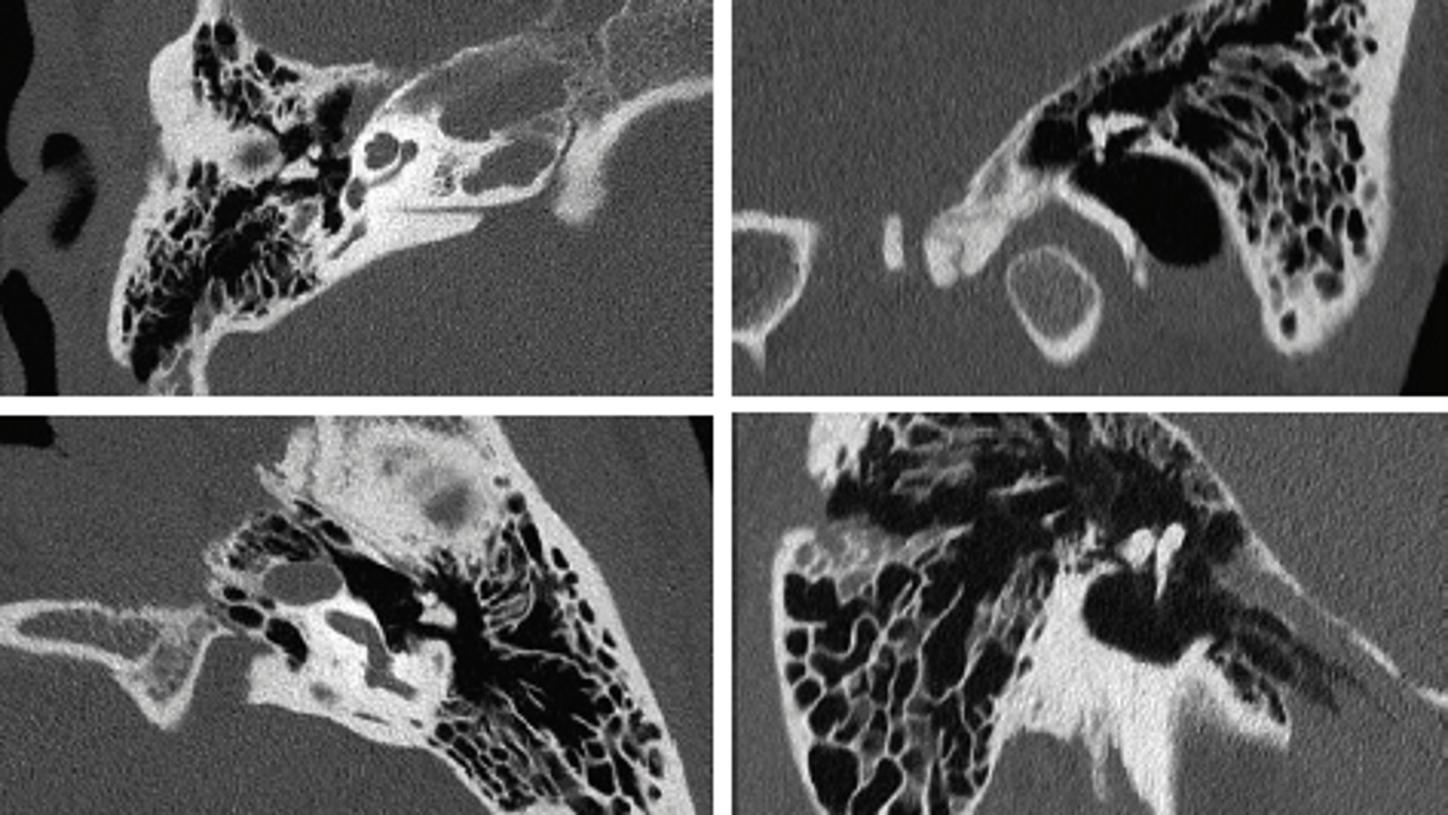

Siemens Healthineers is the technology leader in medical Computed Tomography - we offer the world's fastest rotating CT system1 based on out cutting-edge UFC™ (Ultra Fast Ceramics) detector technology.

After more than 25 years of experience in developing, designing, manufacturing and maintaining CT detector systems, Siemens Healthineers has gained unparalleled insights and know-how in scintillation technology. Well-proven in the clinical setting, UFC offer the outstanding properties that will help advance other fields and applications, too. We now offer our UFC technology to other industries for state-of-the-art X-ray analysis and non-destructive inspections.